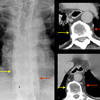

coronal CT